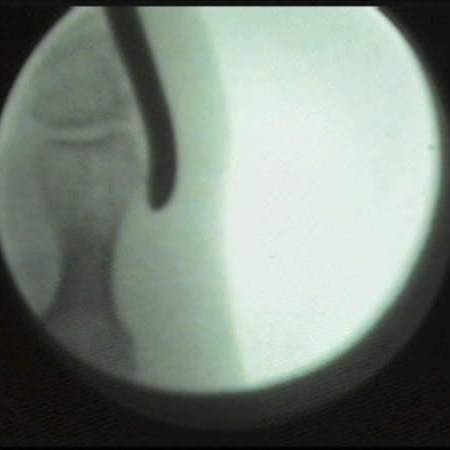

Imagen fluoroscópica de la exóstosis del 5º dedo